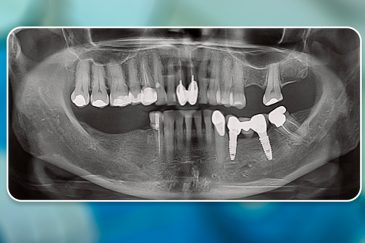

کلینیک تخصصی دکتر حسن روشن طلب با همکاری جمعی از متخصص ایمپلنت دندان و جراح فک و صورت بنام در حال فعالیت می باشد. این مجموعه مأموریت خود را ارائه خدمات تکمیلی دندانپزشکی در زمینه درمان های تخصصی و عمومی به شرح ذیل انجام می شود.

🔸 کاشت ایمپلنت دندان بدون درد

🔸کاشت ایمپلنت فلپ لس یا بدون جراحی و بدون بخیه زیر سه دقیقه

🔸 کاشت دندان یک روزه ( کشیدن و کاشت همزمان )

🔸 ایمپلنت دیجیتال و ساخت روکش دیجیتال

🔸جراحی پیشرفته نظیر سینوس لیفت

🔸ایمپلنت دندان با بیهوشی

انتخاب بهترین متخصص ایمپلنت که به تکنیکهای روز دنیا مسلط باشد، تضمینکننده سلامت فک و زیبایی لبخند شماست. در کلینیک دندانپزشکی دکتر روشنطلب، ما با بهرهگیری از تجهیزات دیجیتال در ۵ شعبه فعال (تهران، اصفهان، رشت و استانبول ترکیه)، خدمات تخصصی کاشت ایمپلنت دندان را برای بیمارانی که کیفیت و دقت برایشان اولویت دارد، ارائه میدهیم. در این متد، پروسه درمان با ظرافت بالا انجام شده؛ راهکاری ایدهآل برای کسانی که به دنبال درمان بدون درد با بالاترین نرخ موفقیت هستند.